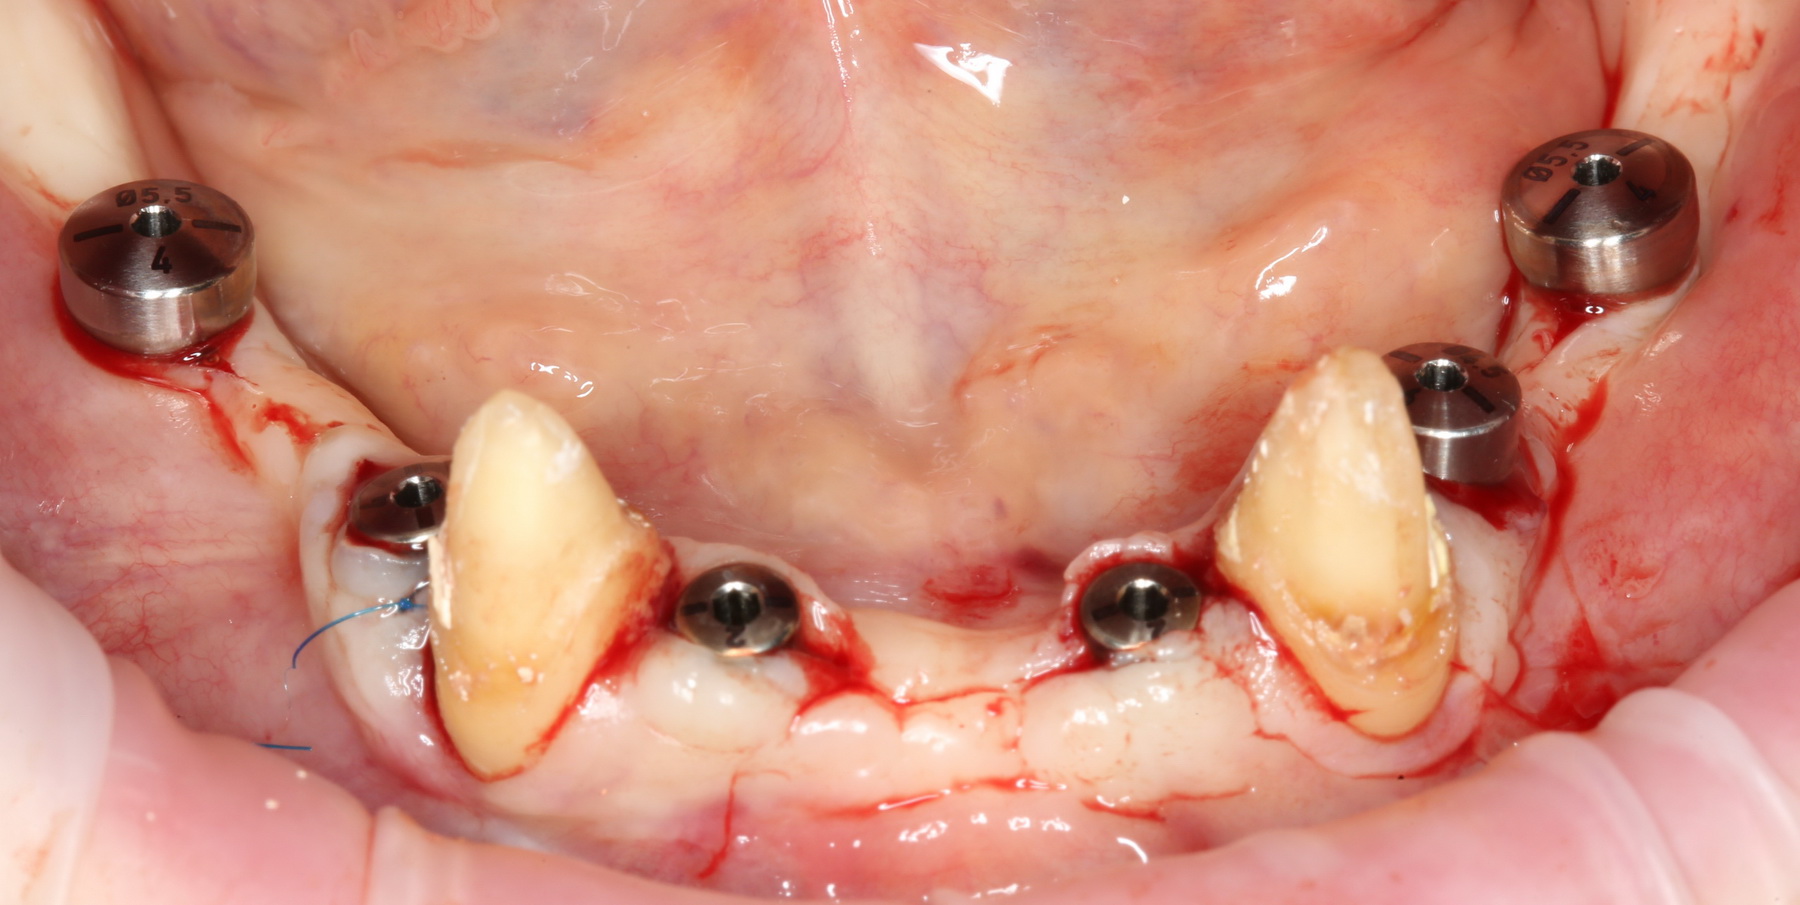

Поэтому мы с Давидом придумали следующее. Мы не стали удалять все зубы, оставили четыре клыка. Это самые большие зубы нашего организма, способные выдерживать значительную нагрузку. Эти четыре клыка Давид использовал как опору временного несъемного (!) протеза, состоящего из восьми (!) единиц на каждой челюсти:

на фотографии вы видите состояние этого протеза, примерно через полгода после начала лечения.

расставить импланты, по шесть штук на каждую челюсть. Разумеется, не все сразу, а постепенно:

А потом еще расставить формирователи десны на установленные импланты: